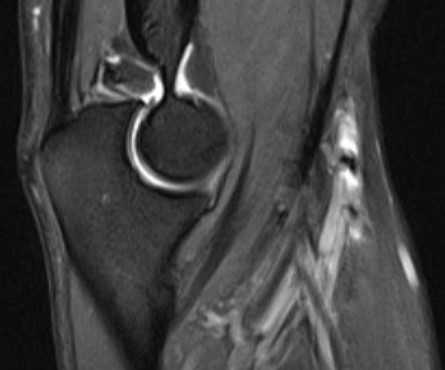

б)МРТ локтевого сустава в корональной плоскости. Общее сухожилие разгибателей в месте прикрепления к латеральному надмыщелку плечевой кости неравномерно утолщено, МР-сигнал от него неоднородно повышен на PD FS-ВИ и Т2-ВИ за счет выраженного отека и разволокнения (признаки латерального эпикондилита), общая целость его не нарушена. Окружающие мягкие ткани с признаками отека.